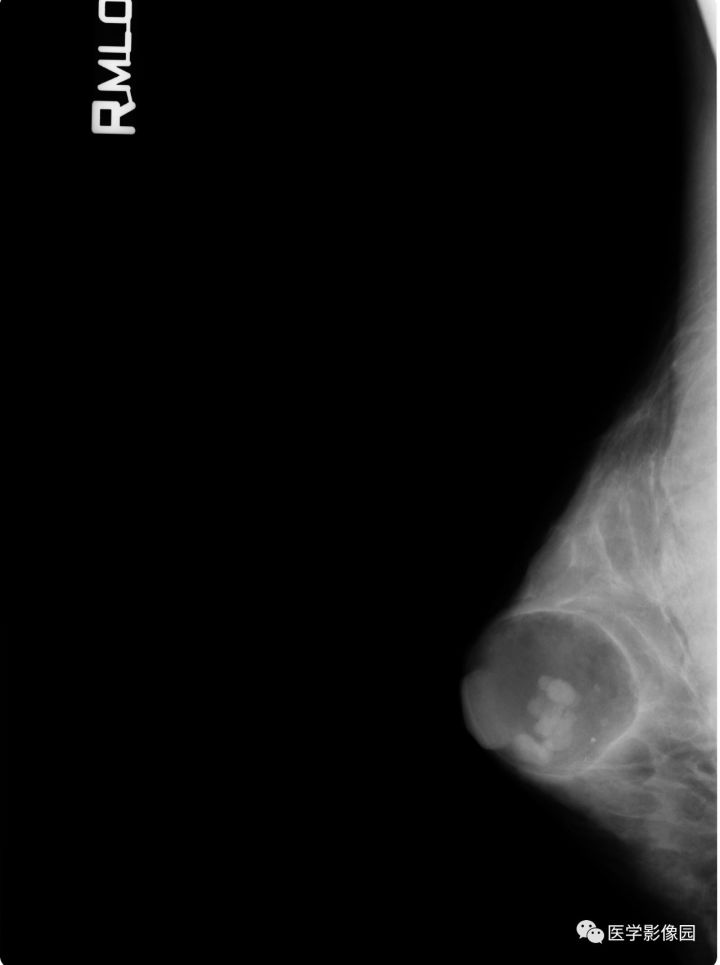

【病例】乳腺错构瘤1例X线钼靶

影像学表现:右乳近乳头处皮下卵圆形低密度影,边界清晰,其中可见多发小结节状高密度影,边界清晰。低密度影内尚可见少许斑点状钙化。

诊断结果:乳腺错构瘤